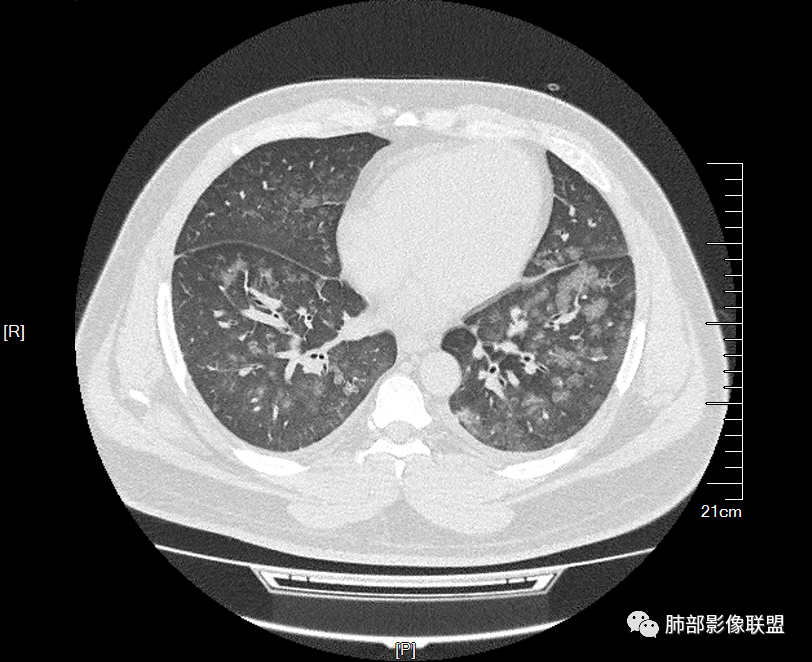

双肺多发弥漫性磨玻璃结节影,大小不一,形态不规则,部分融合,支气管未见明显扩张,部分血管束略增粗,叶裂胸膜增厚,临床有痛风,左足痛6天,考虑:1:痛风结节(一般实性结节,很少磨玻璃结节影)2:血管炎?3:病毒性肺炎(水痘-疱疹肺炎?)

双肺多发腺泡结节及磨玻璃,小叶间隔增厚(大网格状),腺泡结节内及磨玻璃内可见细网格影(小叶内间隔增厚),影像表现符合肺泡出血改变,血肌酐升高,考虑肺肾综合征。鉴别肺水肿。

年轻男性,既往血肌酐升高,左足痛六天入院,有痛风及高血压病史。CT示双肺多发磨玻璃结节影,不规则,部分融合成团或片状,小叶间隔增厚,以双下肺为明显,叶间胸膜亦见增厚。考虑为1.Good-Pasture综合征。2.病毒性肺炎?3.肺水肿?

年轻男性,痛风史,高血压史,肌酐高,左足痛6天入院。胸CT:双肺多发弥漫性磨玻璃结节影,大小不一,部分融合,上中下肺都有,中内带多,胸膜下少。部分血管束略增粗,小叶内间隔、小叶间隔增厚,下肺明显,左室大。叶裂胸膜增厚。临床有痛风,左足痛6天,考虑:心衰、间质性肺水肿?弥漫性肺泡出血?鉴别:MPA,肺肾综合征,痛风结节等。

多发GGO结节,边界清,以全小叶、小叶中心为主:

GGO背景

小叶间隔增厚,无明显重力趋势

少量积液,脂肪肝

这里有一点重力趋势

中轴间质稍增厚

细网格也明显

中轴间质增厚,小叶间隔增厚,小叶内间质增厚,部分重力作用,双侧对称,胸水,按理淋巴道回流受阻有

肺水肿类病变有

问题是腺泡结节如何解释?